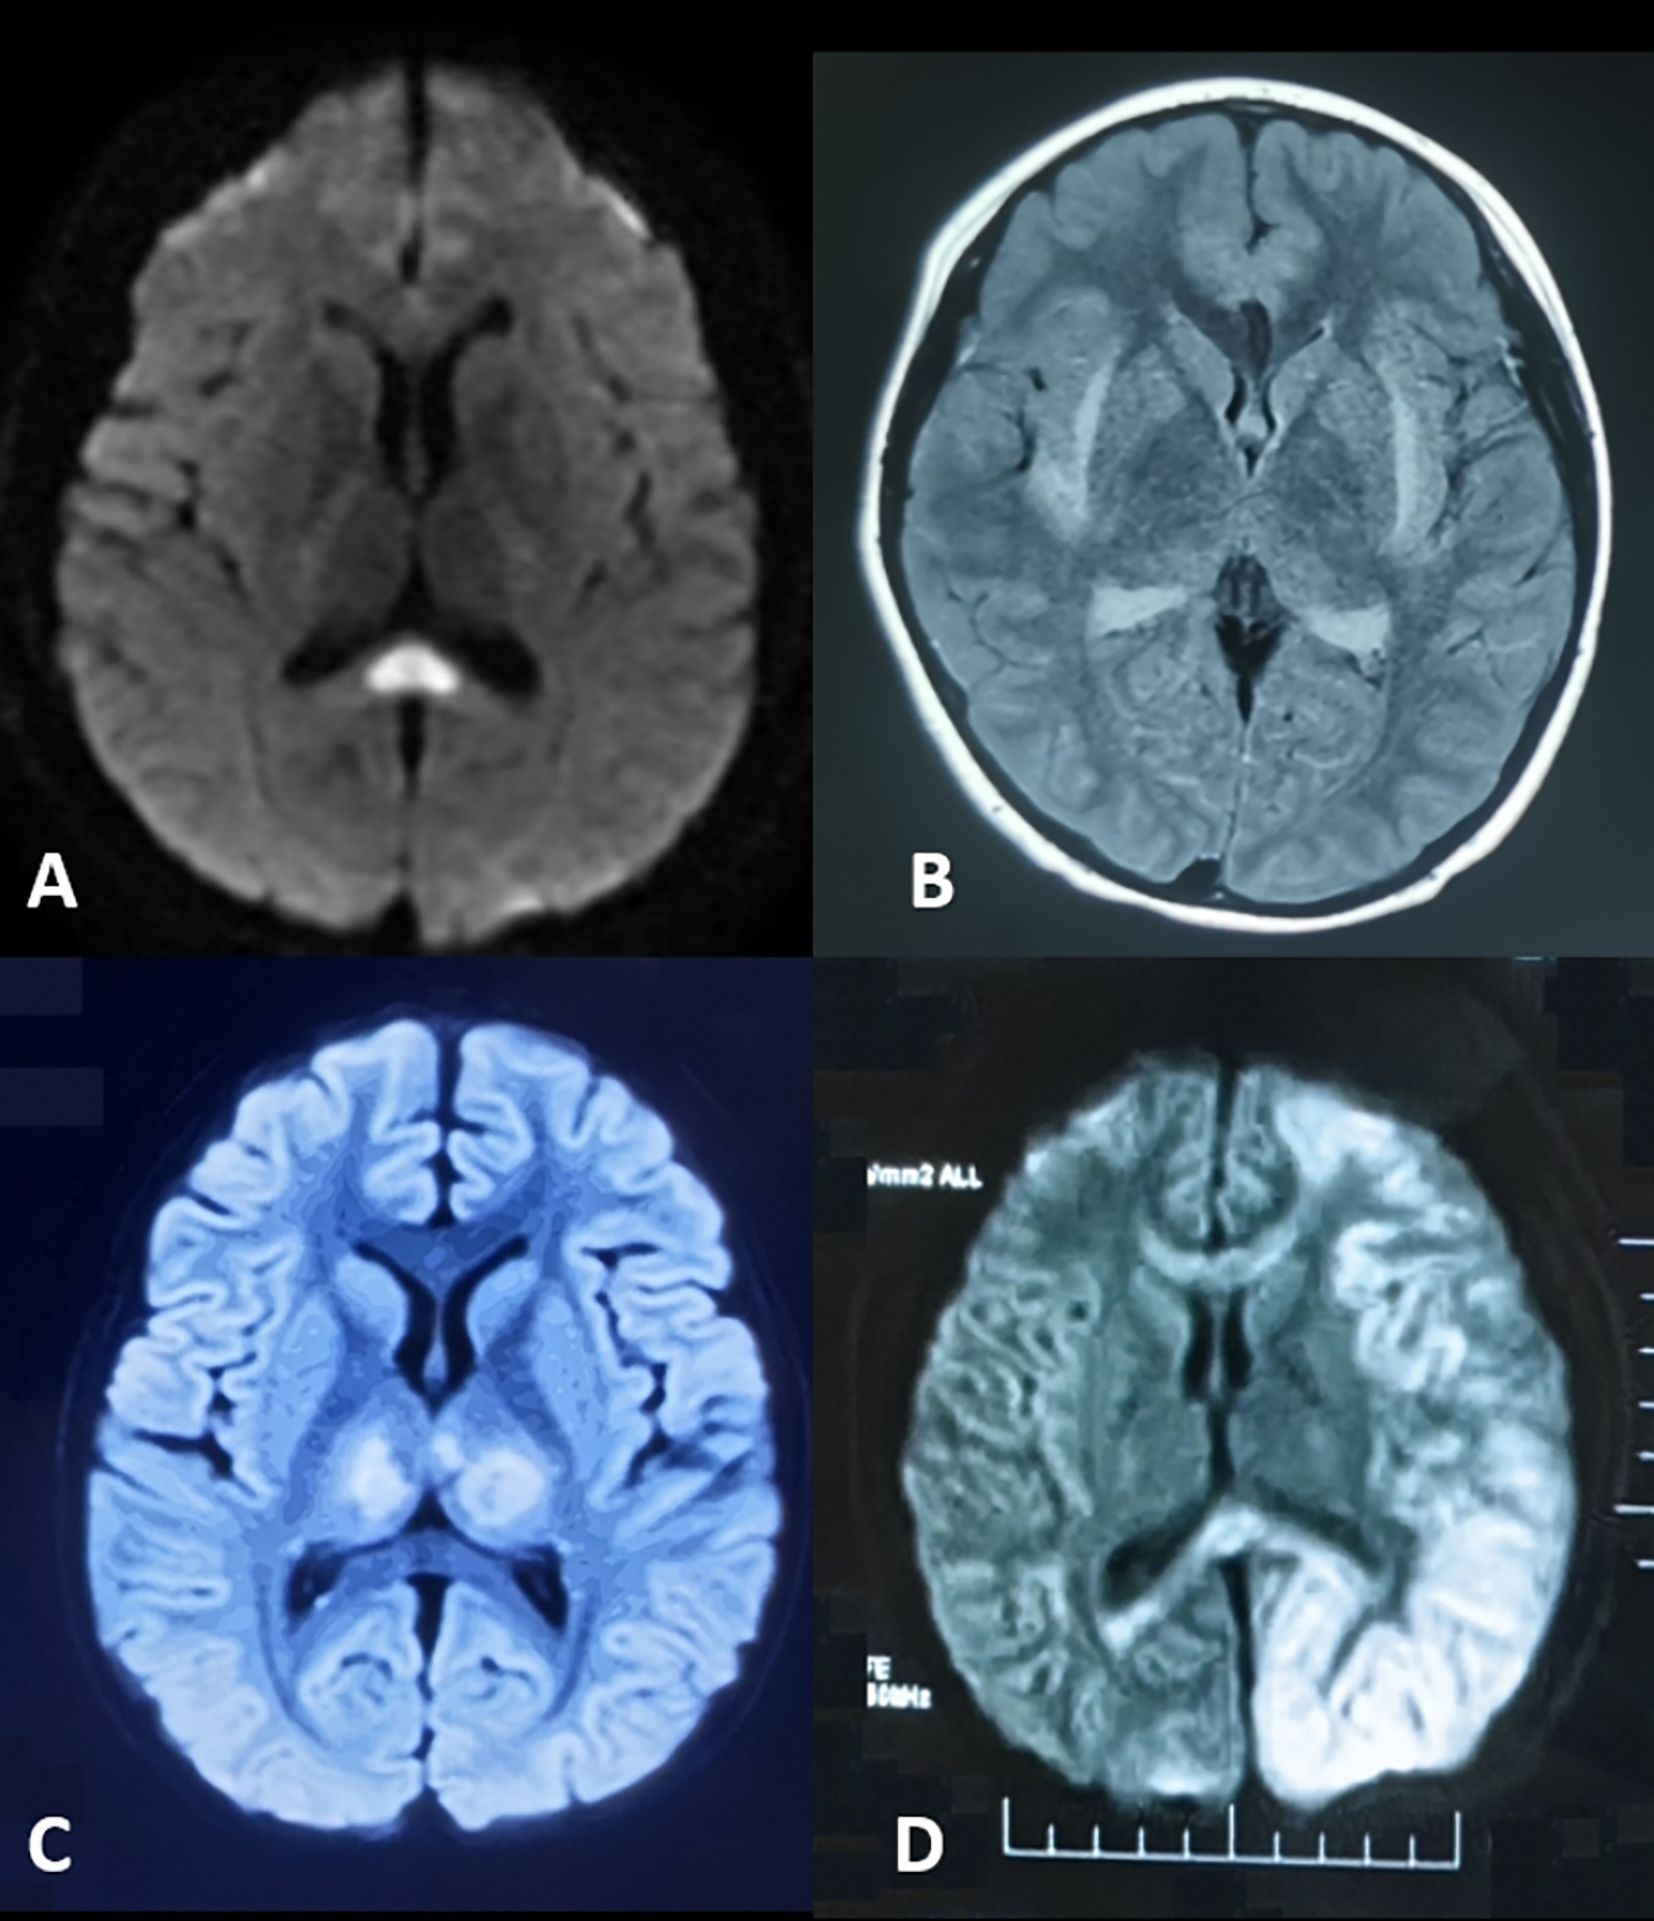

The neuroimaging hallmark of this condition is reversible corpus callosum splenium lesions, manifesting as diffusion-weighted imaging (DWI) hyperintensity with restricted diffusion (Figure 2A). First described by Tada et al. (9) in 2004, MERS was initially identified in a case series predominantly involving Japanese children and adolescents. The etiology of MERS is multifactorial. While early cases were primarily associated with influenza and rotavirus, recent evidence implicates SARS-CoV-2 as an additional trigger (10).

Figure 2. Neuroimaging of parainfectious encephalopathies. (A) Mild Encephalopathy with Reversible Splenial Lesion: splenium of the corpus callosum hyperintensity on diffusion-weighted imaging (DWI). (B) Febrile Infection-Related Epilepsy Syndrome with Claustrum Lesion: bilateral claustrum hyperintensity on T2-weighted and fluid-attenuated inversion recovery (FLAIR) imaging. (C) Acute Necrotizing Encephalopathy: bilateral thalamic hyperintensity on T2/FLAIR imaging. (D) Hemiconvulsion-Hemiplegia Syndrome: left cerebral cortex and subcortical hyperintensity on DWI with corpus callosum involvement and associated edema.

FIRES-C is a distinct subtype of FIRES, marked by claustrum abnormalities on neuroimaging (Figure 2B), which may serve as a diagnostic biomarker. In a cohort reported by Lin Bai et al. (12), 65% of patients were female, with a median age of 20.5 years. The median interval from fever onset to seizures was 5 days. Most presented with generalized tonic-clonic seizures; 45% experienced transient psychiatric or behavioral symptoms, and 50% required ICU admission. MRI typically revealed bilateral claustral lesions, sometimes accompanied by hippocampal signal abnormalities, usually detected around 12.5 days after symptom onset. CSF showed normal or mildly elevated white cell counts. Despite intensive immunotherapy, prognosis was poor, with 58% developing refractory epilepsy at one-year follow-up.

ANE is characterized by rapid-onset encephalopathy, seizures, and focal neurological deficits, often following a febrile illness. Geng Chang et al. reported that in the Chinese population, symptoms typically develop 1~6 days (median 2 days) after respiratory viral infections, presenting as rapidly progressive consciousness disturbances and seizures (13). The hallmark imaging feature is bilateral thalamic lesions (Figure 2C), often accompanied by involvement of supratentorial gray and white matt, brainstem, and cerebellum. Elevated CSF IL - 6 levels and RANBP2 gene abnormalities are key diagnostic markers. ANE is associated with high mortality and disability rates. However, early aggressive immunotherapy may improve outcomes. As a prototypical parainfectious encephalopathy, ANE has been extensively studied in China, especially during COVID-19, advancing our understanding of its mechanisms and management (14–16).

HHS typically occurs in infants and young children. It is characterized by prolonged unilateral clonic seizures during febrile illnesses, followed by persistent hemiplegia. MRI reveals diffuse T2 hyperintensity and restricted diffusion in the affected hemisphere, often with severe edema (Figure 2D). Within one month, the affected hemisphere may show atrophy and hippocampal sclerosis. Approximately 80% of patients develop focal epilepsy.